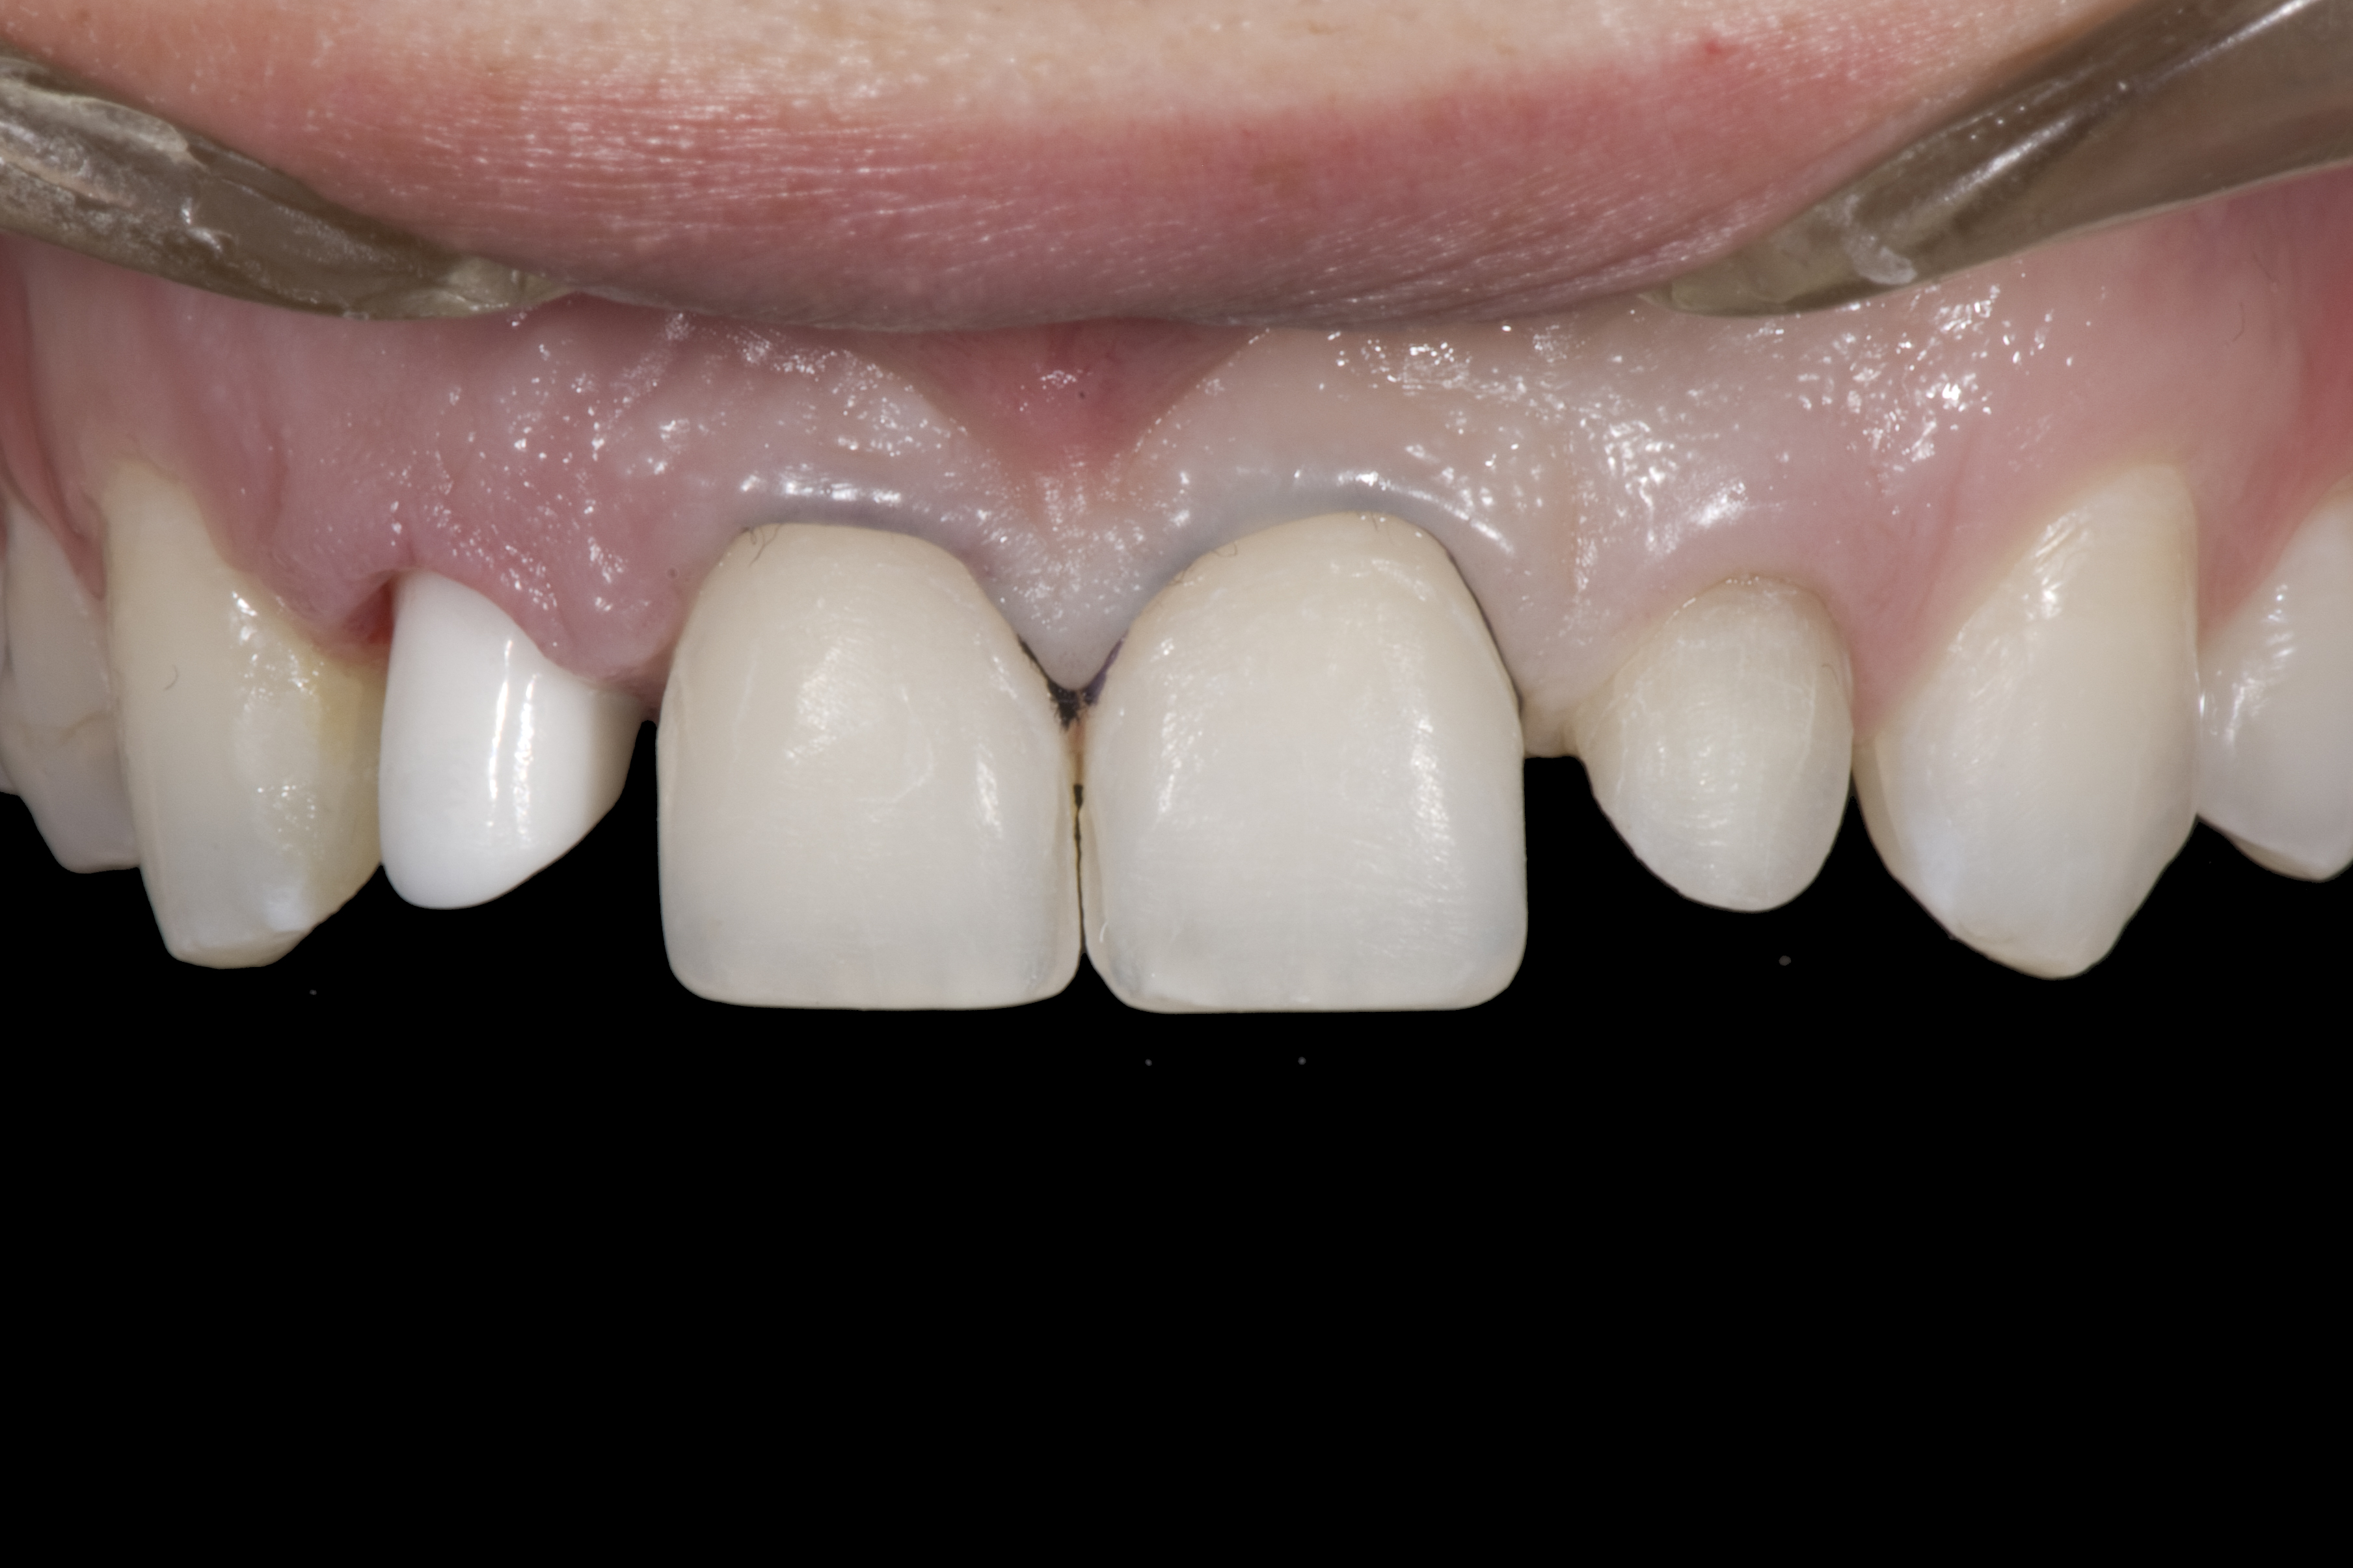

(4.) Double-wing metal resin-bonded (Maryland) bridge replacing the right lateral incisor (facial view).

Figure 4

A 14-year-old patient presented to the office with his mother (Figure 1). His chief complaint involved the large spaces between the teeth created by his missing right maxillary lateral incisor and his small left maxillary lateral incisor. He desired to replace the missing tooth with an implant and create a beautiful smile. Upon examination, he was found to have a class I canine and molar relationship, but because he had a tooth size/arch size discrepancy and space distal to the right central incisor, the remaining incisors had drifted to the right. The left maxillary lateral incisor was peg-shaped and in a cross bite position. Studies have shown a clear association between congenitally missing teeth and reduced tooth size.59-62 Because he was only 14-years-old at the time and could not have implants placed until the cessation of growth (somewhere in the vicinity of 22 years old), he was sent to the orthodontist for alignment of the teeth.16,17 After 2 years of orthodontics, the appliances were removed, and his tooth coloration was improved using carbamide peroxide bleaching (Figure 2). Because some form of provisional needed to be placed until he was finished growing, a double-wing metal resin-bonded bridge was chosen. As discussed earlier, this is the ideal transitional prosthesis for patients that have congenitally missing maxillary lateral incisors. The benefits of this type of prosthesis include its ability to be removed and rebonded during the surgical phase of treatment and its ability to retain the roots in their proper position after orthodontic treatment.16 The final plan for the patient was to increase the width of the central and the maxillary left lateral incisor, utilizing porcelain laminate veneers to achieve the appropriate width/length ratio of 80%. A wax-up was created to idealize tooth size, a putty matrix was made from the wax-up to facilitate bonding of the incisors, and a non-precious, double-wing metal resin-bonded bridge was fabricated for lateral incisor replacement. Once the teeth were bonded to ideal size, the “Maryland Bridge” was fabricated from a polyvinyl arch impression with the newly bonded teeth (Figure 3). The metal frame was cast from a non-precious alloy to allow for fabrication of a very thin frame and to create a better surface for bonding. After sandblasting the internal aspect of the frame with CoJet™ silica (3M ESPE), accomplishing salinization, and executing cementation with a dual-cure resin cement, a fairly good adhesion to the frame was anticipated.29 The enamel surface was etched with phosphoric acid for 30 seconds, the primer (Single Bond Plus, 3M ESPE) was applied to both the internal surface of the sandblasted framework and the etched enamel, and the bridge was cemented with RelyX™ ARC (3M Espe) dual-cured resin cement (Figure 4 and Figure 5).